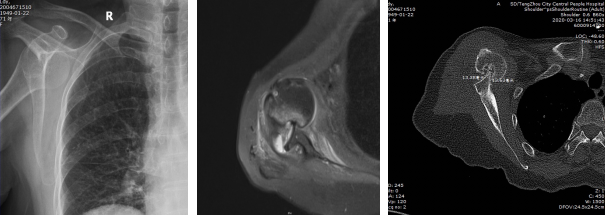

患者術(shù)前檢查:右肩關(guān)節(jié)前脫位,Hill-Sachs損傷,前盂唇損傷,二頭肌腱長頭腱脫位,右肩前脫位并嵌頓且存在骨缺損。

患者術(shù)后檢查:肩關(guān)節(jié)復(fù)位良好

患者老年女性,71歲,40余天前摔傷后出現(xiàn)右肩關(guān)節(jié)疼痛、活動受限,于我市某醫(yī)院就診,經(jīng)過保守治療無效,嚴(yán)重影響生活質(zhì)量?;颊哂?span lang="EN-US">3月13日來我院行右肩MRI檢查示:右肩關(guān)節(jié)脫位、右肩袖損傷、右肩諸肌損傷、右肩關(guān)節(jié)盂唇損傷、右肩關(guān)節(jié)積液,收入院。入院診斷為“1、右肩關(guān)節(jié)陳舊性前脫位 ;2、右肩關(guān)節(jié)Hill-Sachs 損傷;3、右肩關(guān)節(jié)Bankart損傷;4、右肩岡上肌腱損傷 ;5、右肩肱二頭肌長頭腱脫位?!?完善術(shù)前檢查后,為該患者在全麻下進(jìn)行“右肩關(guān)節(jié)鏡松解+肩關(guān)節(jié)脫位復(fù)位+岡上肌腱縫合固定+Bankart損傷修復(fù)+remplissage手術(shù)”,手術(shù)過程順利,術(shù)后恢復(fù)良好,患者肩關(guān)節(jié)癥狀明顯改善。